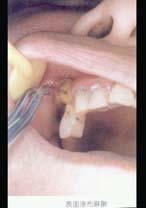

4.患者下颌6根尖部有一瘘孔,有少许脓汁,扣诊(-),无龋坏,不松动。下颌8低位阻生,冠周组织轻度红赤不肿。诊断首先应考虑是  (    )